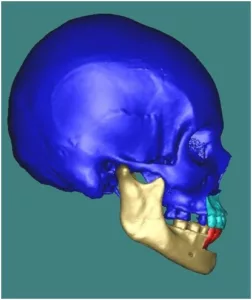

Les ostéotomies combinées

Elles permettent d’agir simultanément sur l’ensemble des éléments anatomiques de la face. En pratique toutes les combinaisons d’ostéotomies sont possibles selon l’anomalie observée. L’ostéotomie Bimaxillaire avec Génioplastie est la plus courante. Elle associe une ostéotomie de Lefort 1 en un ou plusieurs fragments, une ostéotome sagittale bilatérale des branches montantes et une génioplastie.